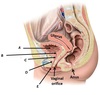

Name structure labelled A

Periosteum